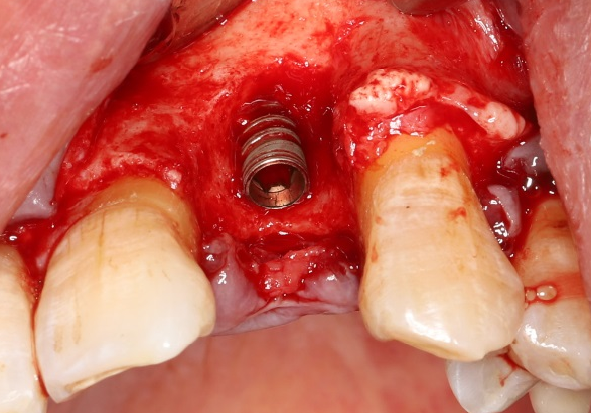

五、标准种植外科备洞程序

使用球钻定位,逐级备孔。

完成备洞。

旋入种植体,初期稳定性为 30N。

直接上愈合基台。